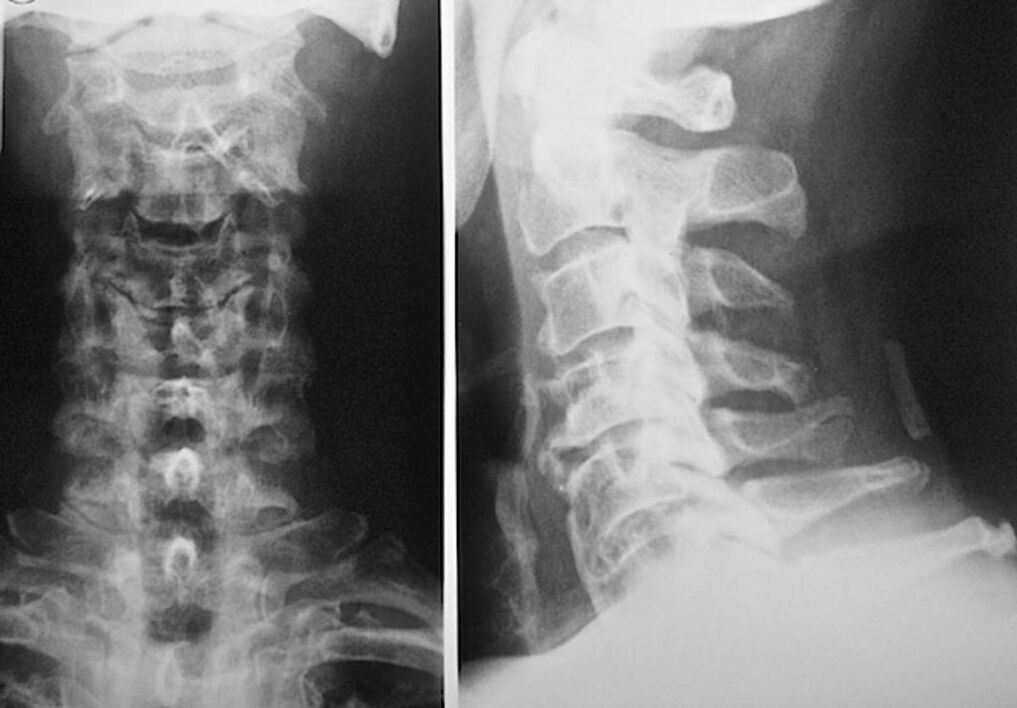

Para o diagnóstico e avaliação precisa da condição dos discos intervertebrais, são utilizados os seguintes métodos de pesquisa:

- Radiografia.

- tomografia computadorizada.

- Tomografia magnética.

- Ultrassonografia dos vasos cervicais.

Cada um deles é completamente seguro para a saúde e não traz nenhuma ameaça de exposição excessiva. O diagnóstico da osteocondrose das vértebras cervicais, cujo tratamento será realizado ao longo da vida, pode ser realizado após um simples exame visual. Qualquer ortopedista pode fazer isso facilmente. Uma exceção é o primeiro estágio da doença, quando não são notadas patologias visíveis da região cervical.